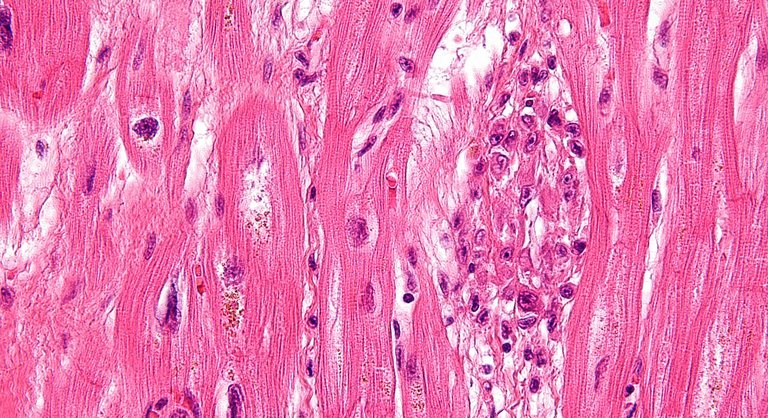

Ikerketa berri onek erakutsi du zelula amek ez dutela eragiten bihotzean zelula berriak sortzea, aurreko ikerketek iradokitzen zuten moduan; baizik eta zelulen transplante horrek erantzun immunologiko akutua eragiten duela, eta, horrek, besteak beste, fibroblastoen jarduera aldatzen duela, eta kaltetutako ehunen propietate mekanikoak hobetzen. Animalietan zelula ama ez bideragarriak txertatuta ondorio berberak lortu zituzten, eta baita erantzun immunologikoa eragiten duen konposatu kimiko bat emanda ere. Hala, ondorioztatu dute erantzun immunologikoa dela, eta ez zelula ametatik ateratzen diren seinaleak, bihotza konpontzen laguntzen duena.